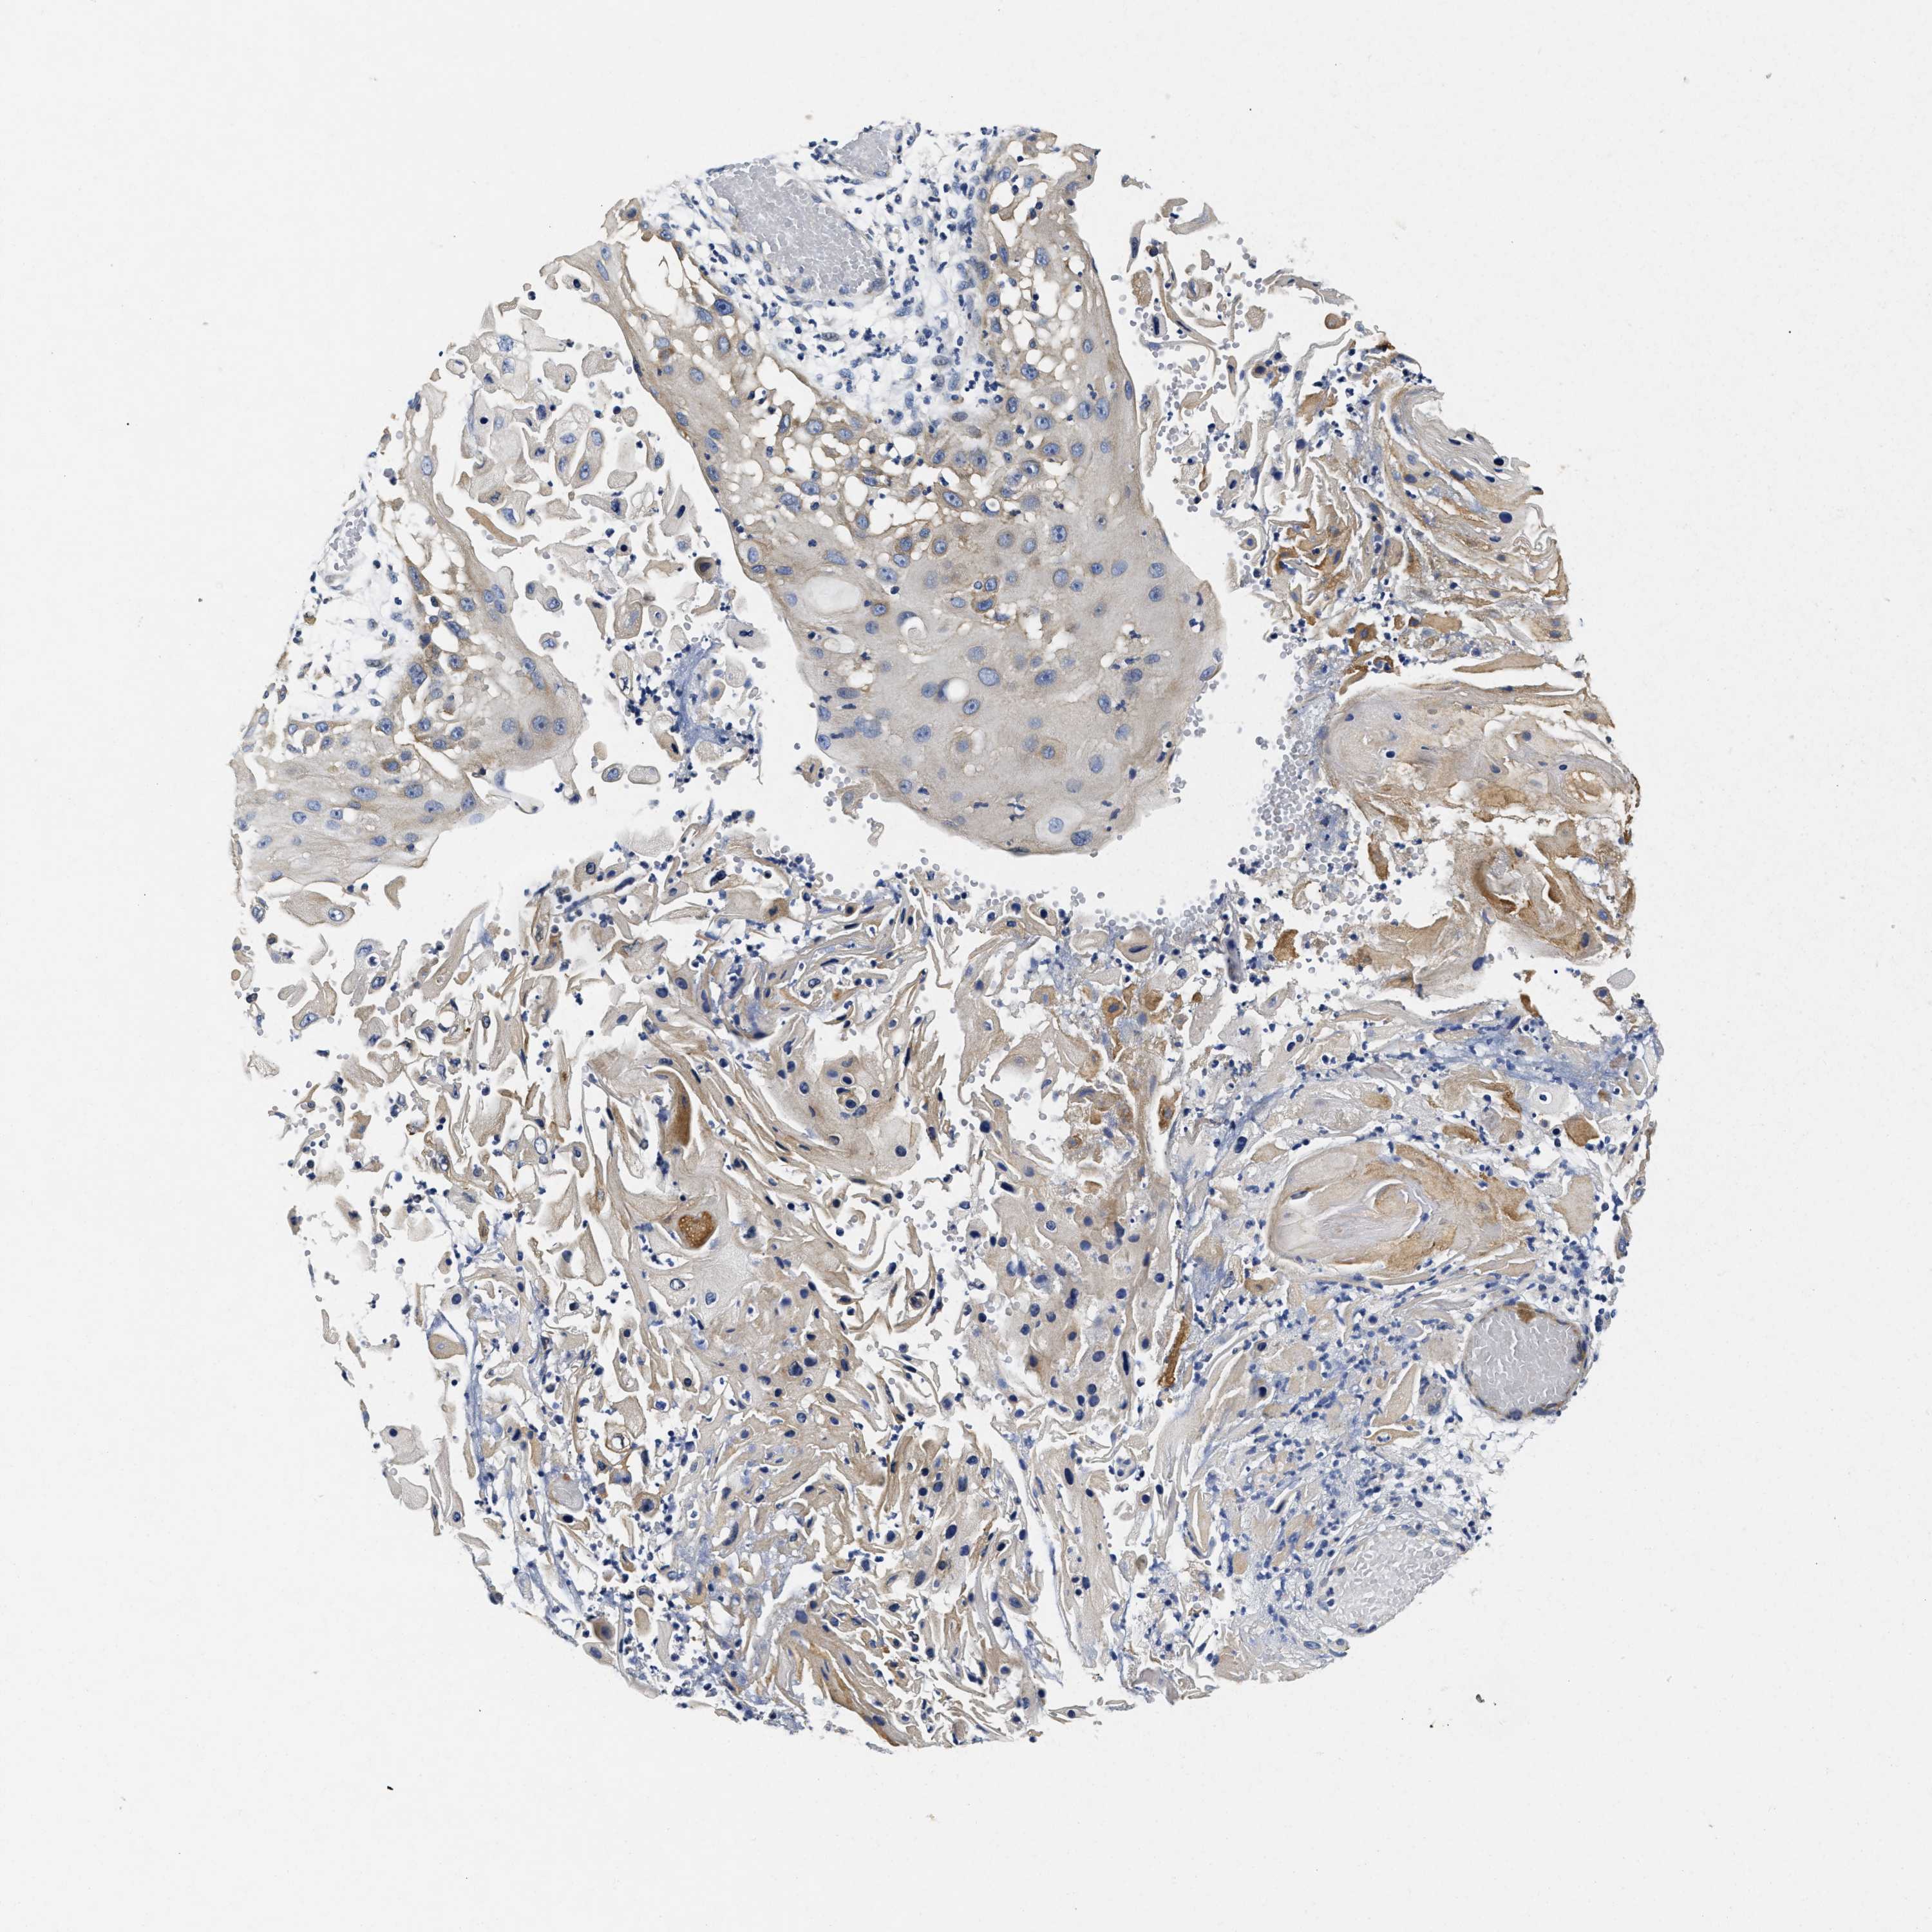

CANCER SKIN CANCER Show tissue menu

Basal cell and squamous cell cancer

SKIN CANCER - Protein expressioni

A mouse-over function shows sample information and annotation data. Click on an image to view it in a full screen mode. Samples can be filtered based on level of antibody staining by selecting one or several of the following categories: high, medium, low and not detected. The assay and annotation is described here.

Each image is clickable and will lead to virtual microscopy that enables deeper exploration of all samples and also displays staining intensity scores, fraction scores and subcellular localization as well as patient and tissue information for each sample.

Antibody HPA007256

Squamous cell carcinoma in situ, NOS

Squamous cell carcinoma, NOS

Squamous cell carcinoma, metastatic, NOS

Basal cell carcinoma